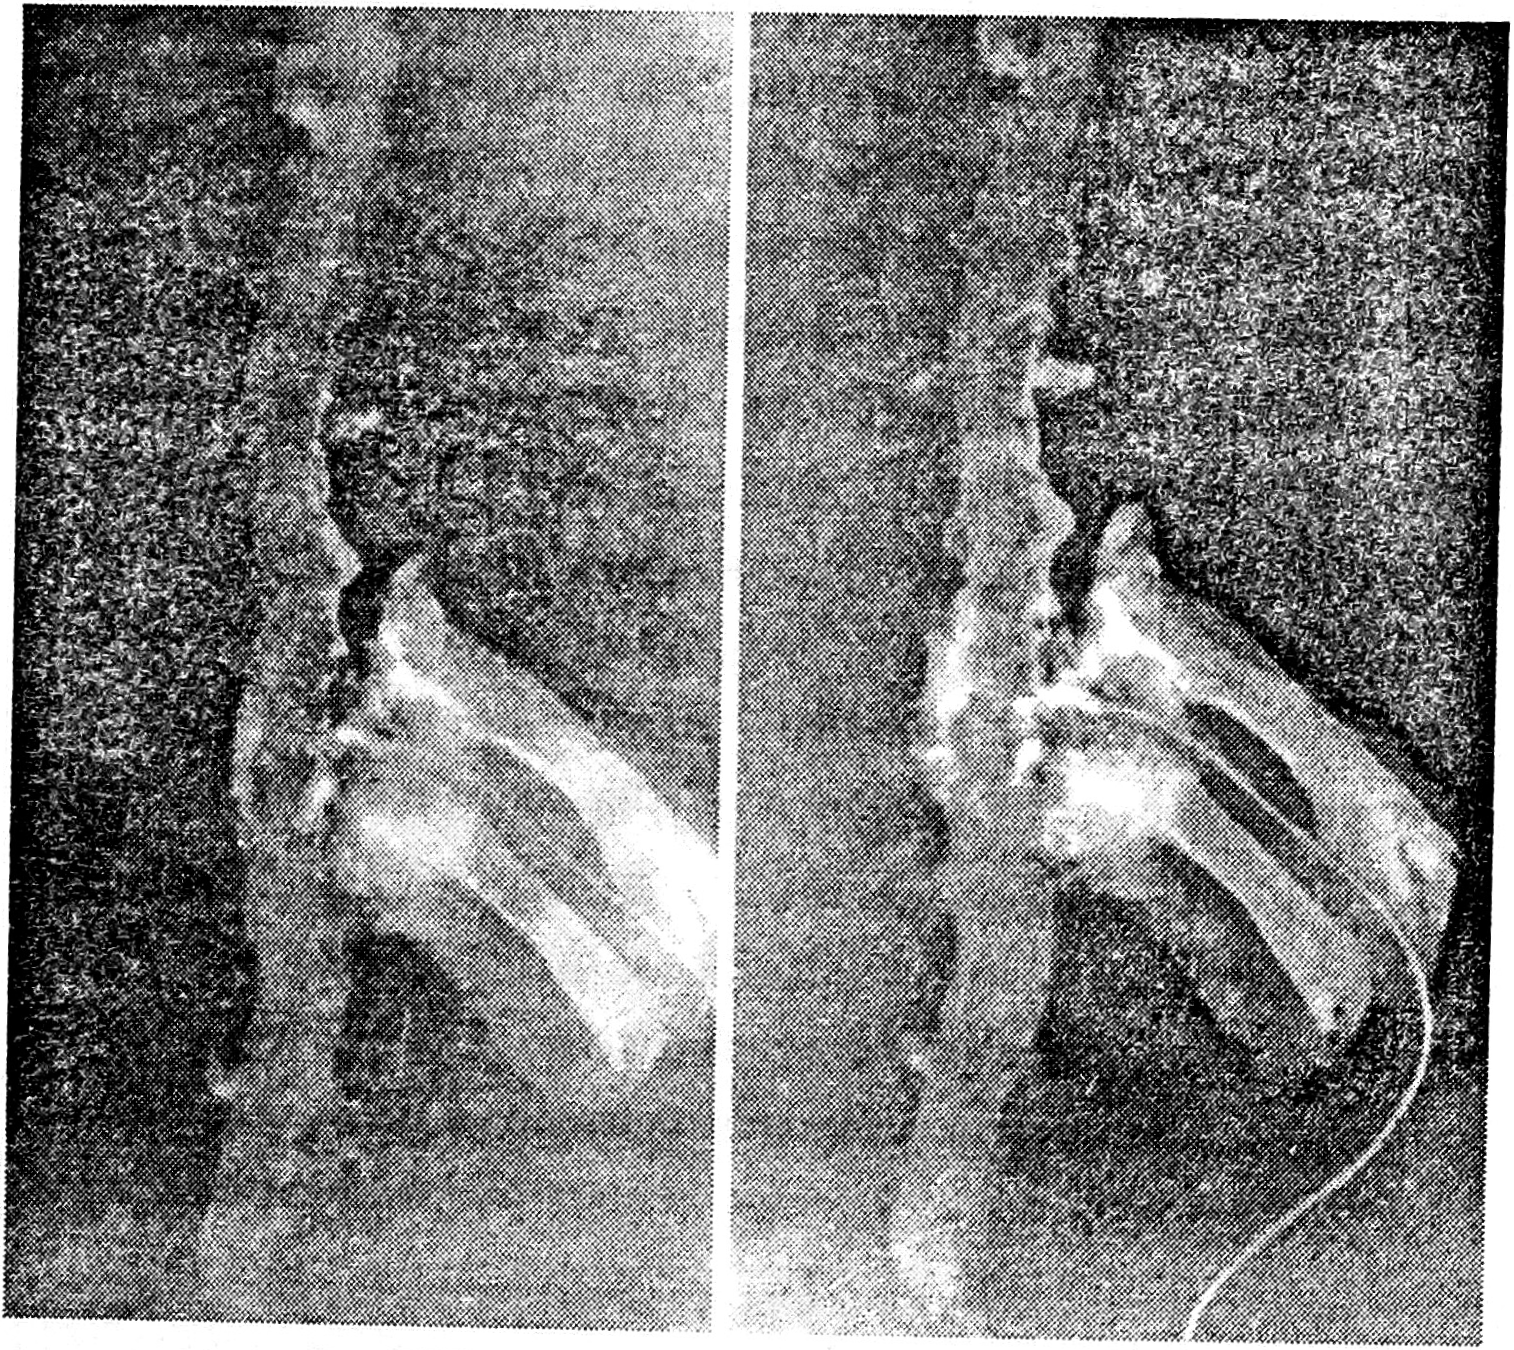

Проходимость анастомозов и величину кровоснабжаемого участка определяли путем контрастирования сосудов 76% раствором верографина. Во всех 4 наблюдениях установлена проходимость анастомозов и наполняемость сосудов сальника по всей поверхности вокруг сегмента спинного мозга (рис. 5).

Рис. 5. Ангиограммы фрагмента сальника, помещенного на спинной мозг.